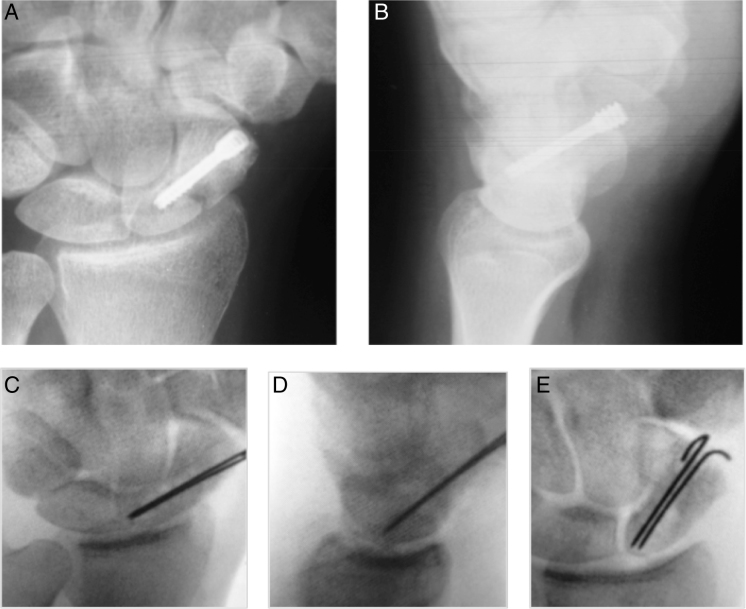

并发症,两名患者出现骨不连,一名舟状骨腰部骨折(图9)和一名近端骨折(图10)。舟状骨腰段骨折,由于加压螺钉的远侧螺纹间距不超过骨折平面的80%,观察到技术故障,因此无法获得稳定。在近端骨折的病例中,由于螺钉头没有完全插入近端而发生了技术故障;失去了稳定性,也没有实现愈合。

图9

腕舟骨骨折,显示骨不连。术后24周出现鼻烟窝疼痛。放射图像(A和B)显示骨不连。通过影像增强器(C–E)获得的图像显示了使用非结构髂骨移植和放置两条克氏针进行新的外科干预。在本例中,使用了volar方法。

根据本研究28例舟骨骨折,92.8%表现为放射学骨愈合,部分作者报道为经皮固定100%骨愈合。在本研究观察到的两例骨不连中,一例为舟骨腰部骨折,另一例为近端骨折,是由技术故障引起的。舟状骨腰段骨折,螺钉远侧螺距不超过骨折平面的80%。在另一个病例中,由于螺钉头没有完全插入近端,因此发生了技术故障;失去了稳定性,也没有实现巩固。本研究中观察到的92.8%的愈合率与Folberg等人和Brutus等人的结果一致,他们分别观察到93.7%和90%的固结率。